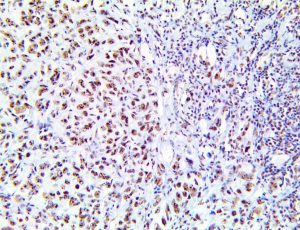

It is the ICU physician who is most likely to witness one of the deadliest manifestations of the abnormal immunological response, the cytokine storm syndrome (CSS). This response is also referred to by some as the cytokine release syndrome (CRS). CSS is characterized by continuous activation and expansion of macrophage and lymphocyte populations, which secrete large amounts of cytokines, causing the cytokine storm. This massive cytokine release is akin to hemophagocytic lymphohistiocytosis (HLH) disease, a syndrome characterized by initial unchecked and persistent activation of cytotoxic T lymphocytes and NK cells.

Clinical and laboratory manifestations of HLH include fever, enlarged liver and/or spleen, neurologic dysfunction, coagulopathy, liver dysfunction, cytopenias (i.e., low levels of erythrocytes, leukocytes, and/or platelets), hypertriglyceridemia, hyperferritinemia, hemophagocytosis, and eventually diminished NK cell activity as the immune system becomes progressively paralyzed. HLH can be familial (primary HLH) or secondary to another disease process (sHLH), such as rheumatic disease, in which it is referred to as macrophage activation syndrome (MAS, characterized by elevated ferritin).